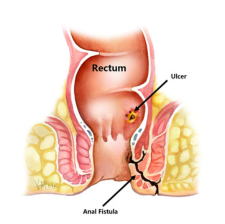

Fistulas

A fistula is an abnormal connection between two body parts, such as an organ or blood vessel and another structure. Fistulas are usually the result of an injury or surgery.Fistulas can occur throughout your body, either between different organs or from

Complex fistulas include those that involve more than 30% of the external sphincter, fistulas with multiple tracts, recurrent fistulas, and those associated with other predisposing factors, including Crohn disease and radiation treatment.

Recurrent Fistulas

As aforementioned, recurrence of anal fistula may be attributed to poor postoperative care after surgery. Hence, regular follow-up with careful office examination is required to ensure proper healing of the surgical wound and detect early recurrence.

Horse Shoe Fistulas

Horseshoe fistulas are deep posterior anal fistulas which extend into the ischiorectal space with either unilateral or bilateral extensions in the shape of a horseshoe.